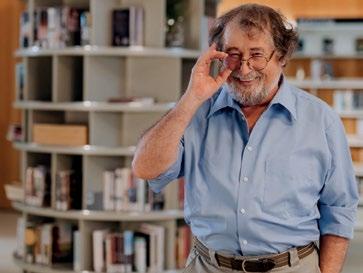

Eelke Lok. Als journalist van Omrop Fryslân draait hij al veertig jaar mee en is hij met name bekend van zijn verslagen van het skûtsjesilen, maar je zou hem tekort doen door hem het stempel sportjournalist te geven, want Lok is allround. Door zijn originele no-nonsense kijk op de wereld weet hij ogenschijnlijk ingewikkelde zaken vaak te relativeren en tot de essentie te herleiden. En dat is ook wat u in de columns van Eelke kunt

Op een boerderij net buiten Makkum woont Peter Nauta (39) met zijn vrouw Aukje Antsje en hun twee zoontjes Hendrik (4) en Ties (2). Tot een jaar geleden hadden Peter en Aukje Antsje het goed voor elkaar. Ze wonen op een mooie plek, hebben op dat moment twee gezonde jongens en leuk werk. Aukje Antsje heeft het gevoel dat het misschien té goed gaat. Ze heeft een voorgevoel dat dit niet zo door kan gaan. Dat voorgevoel blijkt te kloppen…

DDaarover straks meer, maar eerst maken we nader kennis met Peter. Peter Nauta (1984) is er één van een tweeling; hij heeft een tweelingzusje en heeft ook nog een broertje. Peter groeit op in Bolsward, gaat daar naar de basisschool en vervolgens naar AOC Friesland en de middelbare landbouwschool in Sneek.

‘LAATSTE-KANS-EMBRYO’S’

De keuze voor de landbouwschool is logisch, want van jongs af aan is hij met dieren bezig. Na de landbouwschool melkt hij bij verschillende boeren de koeien en daar komt regelmatig de KI langs. Op school vond hij KI (kunstmatige inseminatie) van koeien, het fokken van dieren, al “fantastisch mooi”, en als hij hoort dat er bij de KI een vacature is, solliciteert hij. Peter Nauta: “Sinds december 2007 werk ik bij CRV, de Coöperatie Rundvee Verbetering. Eerst als inseminator, maar inmiddels maak ik echoscopieën om te kijken of een koe drachtig is of een goede cyclus heeft, en ik plaats ‘laatste-kans-embryo’s’ bij koeien die niet drachtig worden, en in het kader van ons fokprogramma genetisch hoogwaardige embryo’s.”

SCHAATSEN EN VOETBAL

Naast zijn interesse voor dieren doet Peter van jongs af aan ook aan sport, met name aan schaatsen. “Wij zijn zowat opgegroeid met de schaatsen aan. Daarnaast ging ik op kaatsen, maar ik heb niet zulke goede ogen, dus ik sloeg vaker mis dan raak.” Lachend: “Het balletje was wat klein. Toen ben ik gaan voetballen; die bal was groter en dat ging een stuk beter. Toen ik zowel met schaatsen als met voetbal wat hogerop kwam, moest ik kiezen. De keuze was snel gemaakt; mijn broertje Frederik en ik wilden verder met marathonschaatsen. Mijn beste prestaties? Bij de B-divisie werd ik Nederlands Kampioen. Bij de A-divisie vierde. En op het Nederlands Kampioenschap ben ik een keer elfde geworden. Toen ik dertig was, ben ik gestopt.”

HUISJE-BOOMPJE-BEESTJE Begin 2017 leert hij Aukje Antsje op de Hoek kennen. Ze blijken veel overeenkomsten te hebben en twee en een half jaar later trouwen ze. Aukje Antsje is zwanger als ze naar hun droomplek, de boerderij bij Makkum, verhuizen. Het woonhuis hebben ze compleet verbouwd. De laatste kamer, de badkamer, is op een zaterdag klaar, en de woensdag erna wordt Hendrik geboren, een zoontje. Het is dan augustus 2020. Ties, het broertje van Hendrik, komt in april 2022 ter wereld. Huisje-boompje-beestje.

“Als er iets met je gezin is, kun

Dan wordt het december 2023 en Hendrik klaagt steeds over buikpijn. De pijn gaat niet over en Aukje Antsje heeft een voorgevoel… “Volgens de huisarts was het obstipatie en dat zou met poeders over moeten gaan”, blikt Peter terug. “Het ging niet over, en we zaten regelmatig bij de Dokterswacht waar we steeds te horen kregen dat hij veel moest drinken en poeders moest nemen. Hij bleef maar kwakkelen en op 23 december gingen we weer naar de Dokterswacht. Er was een Turkse huisarts die het niet vertrouwde en wilde dat de kinderarts ernaar zou kijken. Die zei dat ze Hendrik niet hoefde te zien omdat het obstipatie was. De huisarts hield voet bij stuk, daarna heeft de kinderarts hem toch gezien en zij zei weer dat het obstipatie was. Toen we wegliepen, kwam de huisarts achter ons aan en zei dat we na de feestdagen bloed moesten laten prikken.

Tijdens kerst werd het steeds erger. Hendrik zat hele avonden op de pot, maar er kwam niks. Op Nieuwjaarsdag gingen we weer naar de Dokterswacht en weer werden we naar huis gestuurd. Op 2 januari had Hendrik helemaal niks gegeten of gedronken. Op een gegeven moment spuugde hij en kwam er ontlasting uit. Je schrikt je kapot. Via de huisarts kwamen we in het ziekenhuis, waar ze een klysma hebben geprobeerd, maar er kwam weer niks. Ook zijn er foto’s gemaakt, maar ze zagen niets.”

DOOR DE GROND”

“De volgende dag kreeg Hendrik een MRI en daar zagen ze die…” – Peter Nauta vertelt geëmotioneerd verder – “die tumor in zijn lymfeklieren. Die was vijf en een halve centimeter groot en blokkeerde de darmen. Als je dat hoort, zak je door de grond. Je bent hélemaal nergens, en denkt dat je hem kwijtraakt. Aukje Antsje was aardig sterk, vanwege haar voorgevoel dat er iets ergs ging gebeuren. Zij dacht: ‘Dit is het dus’. Binnen het uur reden we met gillende sirenes naar het PMC, het Prinses Máxima Centrum in Utrecht. De chirurg wilde diezelfde avond al opereren, omdat het een heel agressieve vorm van kanker was. Wij waren allang blij dat er wat gedaan werd. De operatie duurde twee uur. De tumor, een lymfoom, is eruit gehaald en de operatie was geslaagd. De kans op genezing was negentig procent. Dat gaf me kracht. Het ene moment denk je dat je hem kwijtraakt, en kort daarna hoor je dat er negentig procent kans op genezing is. Ik was heel positief. Als ze tegen mij zeggen dat hij negentig procent kans heeft om te herstellen, is het bij mij honderd procent. Aukje Antsje was bang dat hij bij die tien procent ging horen. Zij heeft echt een rottijd gehad. Ik wilde daar niet aan denken.”

VIJF MAANDEN SONDEVOEDING, VIJF MAANDEN

CHEMO

“Hendrik moest na de operatie vijf dagen

herstellen voordat de chemo begon. De rotste bijwerking was dat alle slijmvliezen van mond tot kont werden aangetast. Dat betekent dat zijn keel, zijn mond en de binnenkant van zijn darmpjes helemaal open waren. Slikken deed hartstikke zeer. Hij heeft vijf maanden sondevoeding gehad, omdat hij niet at. Hij ging van twintig naar dertien kilo. Soms kon hij de sondevoeding niet aan, en kreeg hij voeding via het bloed. Ik heb weleens gedacht: ‘Die kanker is weg, maar straks sterft hij ergens anders aan.’

Na een week chemo mocht Hendrik drie weken naar huis om te herstellen, maar als hij koorts had, moest hij binnen het uur in een ziekenhuis zijn. Na de eerste kuur waren we een dag thuis, toen hij koorts kreeg. Wij waren natuurlijk in paniek en wilden zo snel mogelijk naar Leeuwarden. Ties brachten we snel naar beppe. De volgende dag gingen we van MCL naar PMC waar Hendrik antibiotica kreeg. Wij bleven bij hem. Na de volgende chemokuur deed ik mijn jas aan om naar buiten te gaan en toen zei Ties helemaal in paniek: ‘Jas aan, jas aan.’ Hij sliep ook niet goed, dus wij dachten: dit moet anders. Vanaf toen wisselden Aukje Antsje en ik elkaar af: één van ons was bij Ties, de ander bij Hendrik.

Hendrik heeft vijf maanden chemo gehad en daarna is hij schoon verklaard. Fantastisch! We hebben nu om de twee maanden controle. De eerste vijf jaar blijft hij sowieso onder controle, maar de frequentie zal afnemen. Als je hem nu ziet, merk je niks

aan hem. Hij speelt, gaat naar de peuters, je ziet er niks meer van. Het is wel bijzonder hoe flexibel kinderen zijn.”

GENIETEN VAN KLEINE DINGEN

“Als je zoiets meemaakt, het klinkt als een cliché, leer je weer genieten van kleine dingen. Laatst zagen Aukje Antsje en ik hoe Hendrik en Ties samen in de tuin speelden, en we zeiden: ‘Goh, dit is genieten!’ Iets wat daarvoor zo vanzelfsprekend was. Ook heb ik gemerkt dat je andere dingen heel gemakkelijk kunt loslaten als zoiets gebeurt. Als er iets met je gezin is, kun je niet goed functioneren. Je wereld staat op de kop. Wat ik heel bijzonder vind is, hoe vrienden en familie voor ons klaarstonden. Zij hebben er onder andere voor gezorgd dat hier iedere dag warm eten voor ons was. Dat heeft ons zó geholpen. Echt fantastisch! En wat nog meer fantastisch is: in maart verwachten wij ons derde kind.”

DRAAIEND RAD OP BOLLLETONGERSDEI “Kinderkanker was altijd een ver-van-ons-bedgebeuren. Maar nu weet je dat wetenschappelijk onderzoek de kans om kanker te overleven groter maakt en wil je er alles aan doen om te helpen. Momenteel geneest 81 procent van kinderkanker; dat moet naar honderd procent. Daarom hebben we sinds februari met allerlei acties geld ingezameld. In juni hebben we een cheque van bijna 15.000 euro overhan-

“Wat het Prinses Máxima Centrum betreft: je wilt er niet zijn, maar als je er móét zijn, dan is het qua liefdevolle zorg en expertise de beste plek die je je kunt wensen”

digd aan het Prinses Máxima Centrum in Utrecht. Wat het PMC betreft: je wilt er niet zijn, maar als je er móét zijn, dan is het qua liefdevolle zorg en expertise de beste plek die je je kunt wensen.”

Op 29 september deed Peter Nauta, gesteund door zijn collega’s, mee aan de Run voor KiKa in Almere om geld in te zamelen voor de stichting Kinderen Kankervrij. “En op Bolletongersdei, donderdag 3 oktober, sta ik met een draaiend rad in Bolsward om geld in te zamelen”, kondigt hij de eerstvolgende actie aan.

SCHAATSEN VOOR KIKA

En er gebeurt méér. Peter Nauta was afgelopen jaar als figurant-schaatser te zien in Musical De Tocht in Leeuwarden. Met een groep van bijna dertig figurant-schaatsers uit de musical vertrekt hij komende winter naar de Weissensee in Oostenrijk om er op vrijdag 24 januari de Alternatieve Elfstedentocht te rijden met als doel geld op te halen voor KiKa. “We streven naar een bedrag van dertigduizend euro”, zegt Peter.

Lezers van GrootBolsward-IJsselmeerkust die Peter Nauta en het Team De Tocht op 24 januari op de Weissensee willen steunen, en daarmee dus geld voor KiKa willen doneren, kunnen dit doen via de QR-code bij dit artikel.